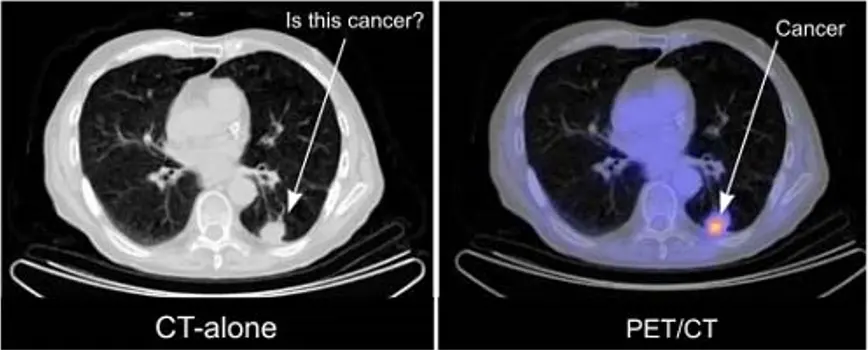

PET是惟一可在活体上显示生物分子代谢的影像技术,被广泛用于多种疾病的诊断与鉴别诊断、病情判断、疗效评价、脏器功能研究和新药开发等方面。例如:利用恶性肿瘤组织的高代谢特点可对病变进行诊断和分析(如下图所示)。

图3. PET成像在肿瘤诊断上的应用,常与CT(computerized tomography)共同使用,利用PET可以观察到肿瘤组织的代谢情况,从而提高诊断和治疗的效果。